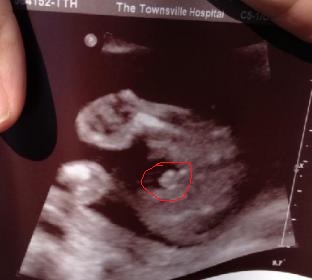

I had my 19wk scan today, tech said baby is another boy. She also stated that she didnt see testicles. Dh and I didnt see an obvious penis.

She gave me this bottom potty shot to take home. If she didnt see testicles then what is this a picture of????